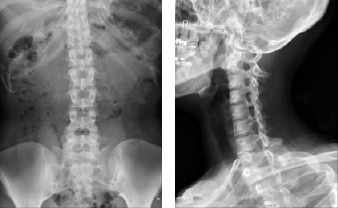

一般撮影

- ・平面の撮影をします。

- ・骨折や病変が存在するかの検査時に使用します。

一般撮影の撮影画像

骨の画像

胸の画像